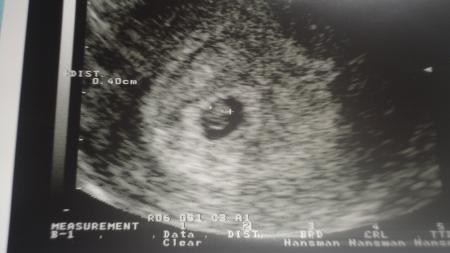

Hallo ihr Liebe!!! Heut früh ein bisi rosa Ausfluss, wieder schock! Dann zum vereinbarten FA-Termin, mein Freund ist auch mitgekommen :) UND.... beim Ultraschall sah man den kleinen Krümmel ( 4mm) und supertoll das Herz schlagen!!!!!!!!!!!!!!!!!!!!!!!!! Freu freu, das ist ein tollllles Weihnachtsgeschenk!! Hoff euch geht es auch sooo gut!! Ganz liebe Grüße Manuela

so und nun noch ein Foto von unseren Zwuck :) :) Echt arg!!! Am Sonntag sah der Dok im kH noch keine Fruchtanlage und nun ist es schon 4mm und das Herz schlägt!!